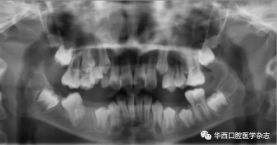

全景片及錐形束CT(cone beam computed tomo-graphy,CBCT)三維重建影像顯示:46牙胚存在,牙冠朝向遠中,且牙長軸與下頜骨下緣接近平行,遠中根發(fā)育約為根長2/3,近中根發(fā)育約為根長1/2且稍向下彎曲,近中根與45牙關系密切,下頜其余牙胚正常(圖2、圖3)。

圖 6 治療1個月全景片

圖 7 治療5個月全景片